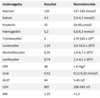

- Herefter udleveres kort med svar på parakliniske undersøgelser (se billede).